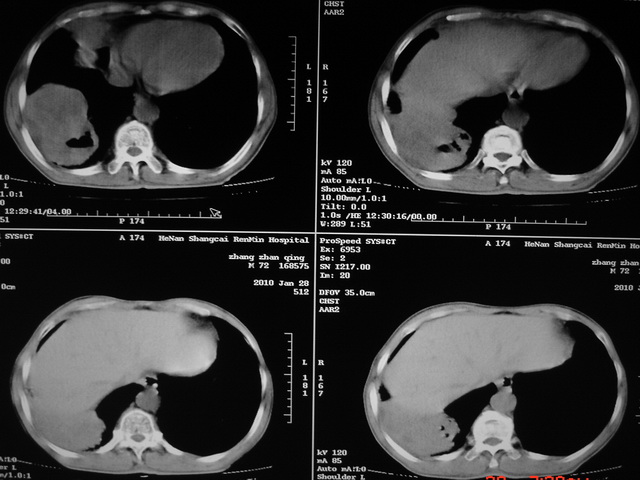

标题: CT24386:M 72岁农民 右侧胸痛6月余,咳嗽,无发热、咯血等 [打印本页]

xx m 72岁农民 右侧胸痛6月余,咳嗽,无发热、咯血等

右下周围型肺癌,并右肺门、纵膈淋巴结、内乳淋巴结转移,右胸膜转移累及前胸壁。鉴别:脓肿、tb、淋巴瘤。病理类型可能为大细胞型。

这个病人有点复杂了,上纵隔像是占位,右肺下叶见壁光整厚壁空洞加液平,像是肺脓肿,中叶病灶牵涉到胸膜及胸壁,形态看像是炎性病变,总之不能除外恶性病变,还是穿刺或增强后再说。

支持2搂,考虑右肺下叶周围性肺癌伴肺门及纵膈淋巴结转移!右侧前纵膈病灶,还是一元论考虑为胸壁或胸膜转移瘤。

支持 右肺下叶周围型肺癌并右肺门、纵膈淋巴结、内乳淋巴结转移,右胸膜转移累及前胸壁。